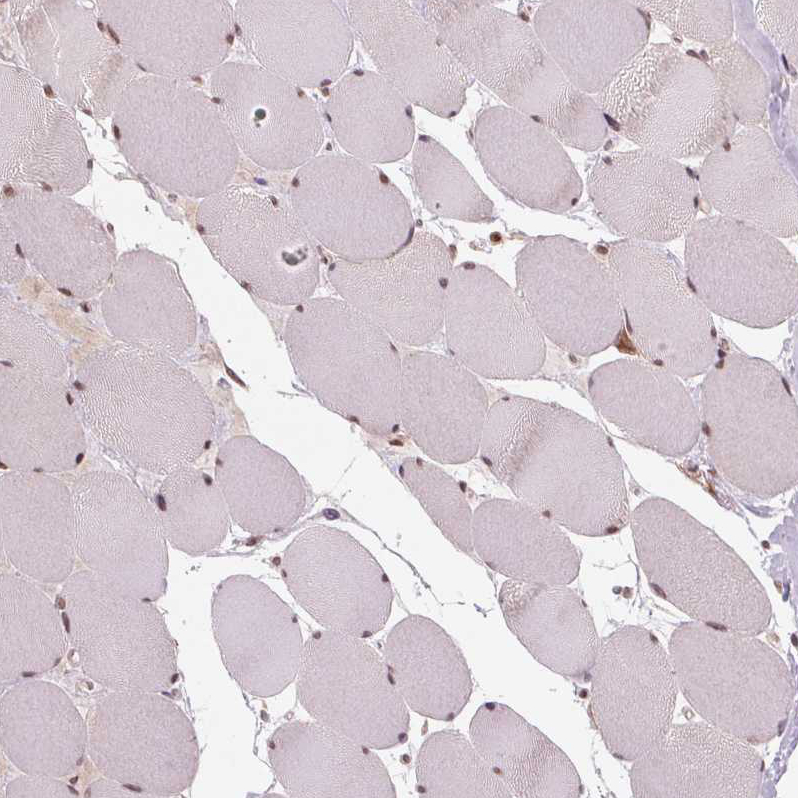

Immunohistochemical staining of human spleen shows moderate cytoplasmic positivity in cells in red pulp.